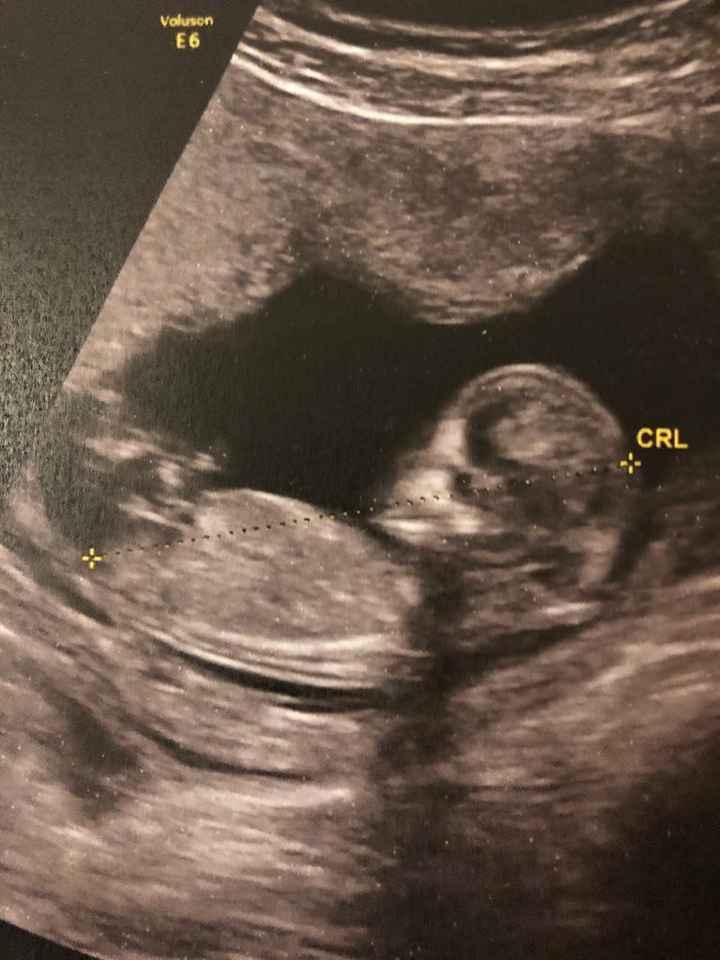

Nub theory 2

Ragazze ho fatto oggi la traslucenza nucale...l unica eco decente e' questa (si vede male lo so...)...qualche esperta di nub theory si vuole sbilanciare? Oggi c era un sostituto del mio ginecologo e purtroppo non mi ha saputo dire niente... secondo il metodo Ramzi e' femmina, secondo le fasi lunari maschio... uffa sono troppo curiosa... 😁